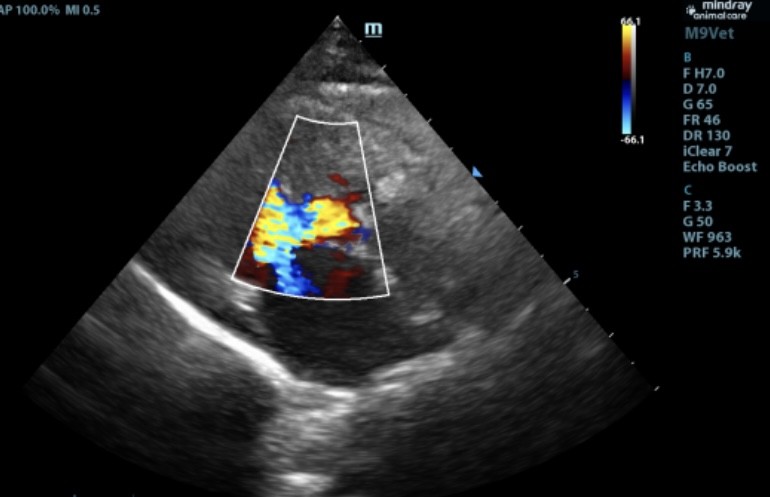

心脏疾病是老年宠物常见的健康问题,医院配备了进口心脏彩超设备,能够精准诊断各种心脏疾病。负责心脏科的张培培医生擅长心肌病、肥厚型心肌病等复杂心血管疾病,并提供长期药物管理和定期随访服务,帮助宠物维持良好的心脏功能。

此前,6岁的猫咪因抽搐呕吐,后腿无力就诊,经查后发现左心室心肌及室间隔厚度增加,主动脉和二尖瓣均存在反流,诊断为肥厚型心肌病。口服利尿剂和抗血栓药物,一周后精神好转,再无出现抽搐、呕吐、后腿无力等现象。